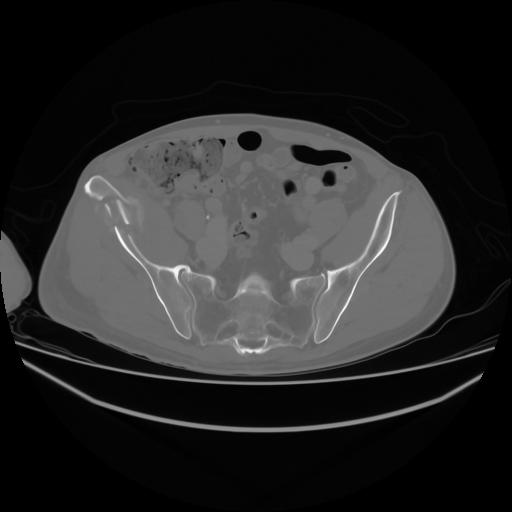

4 CUERPO,CE,Axial,3.0,CUERPO,,